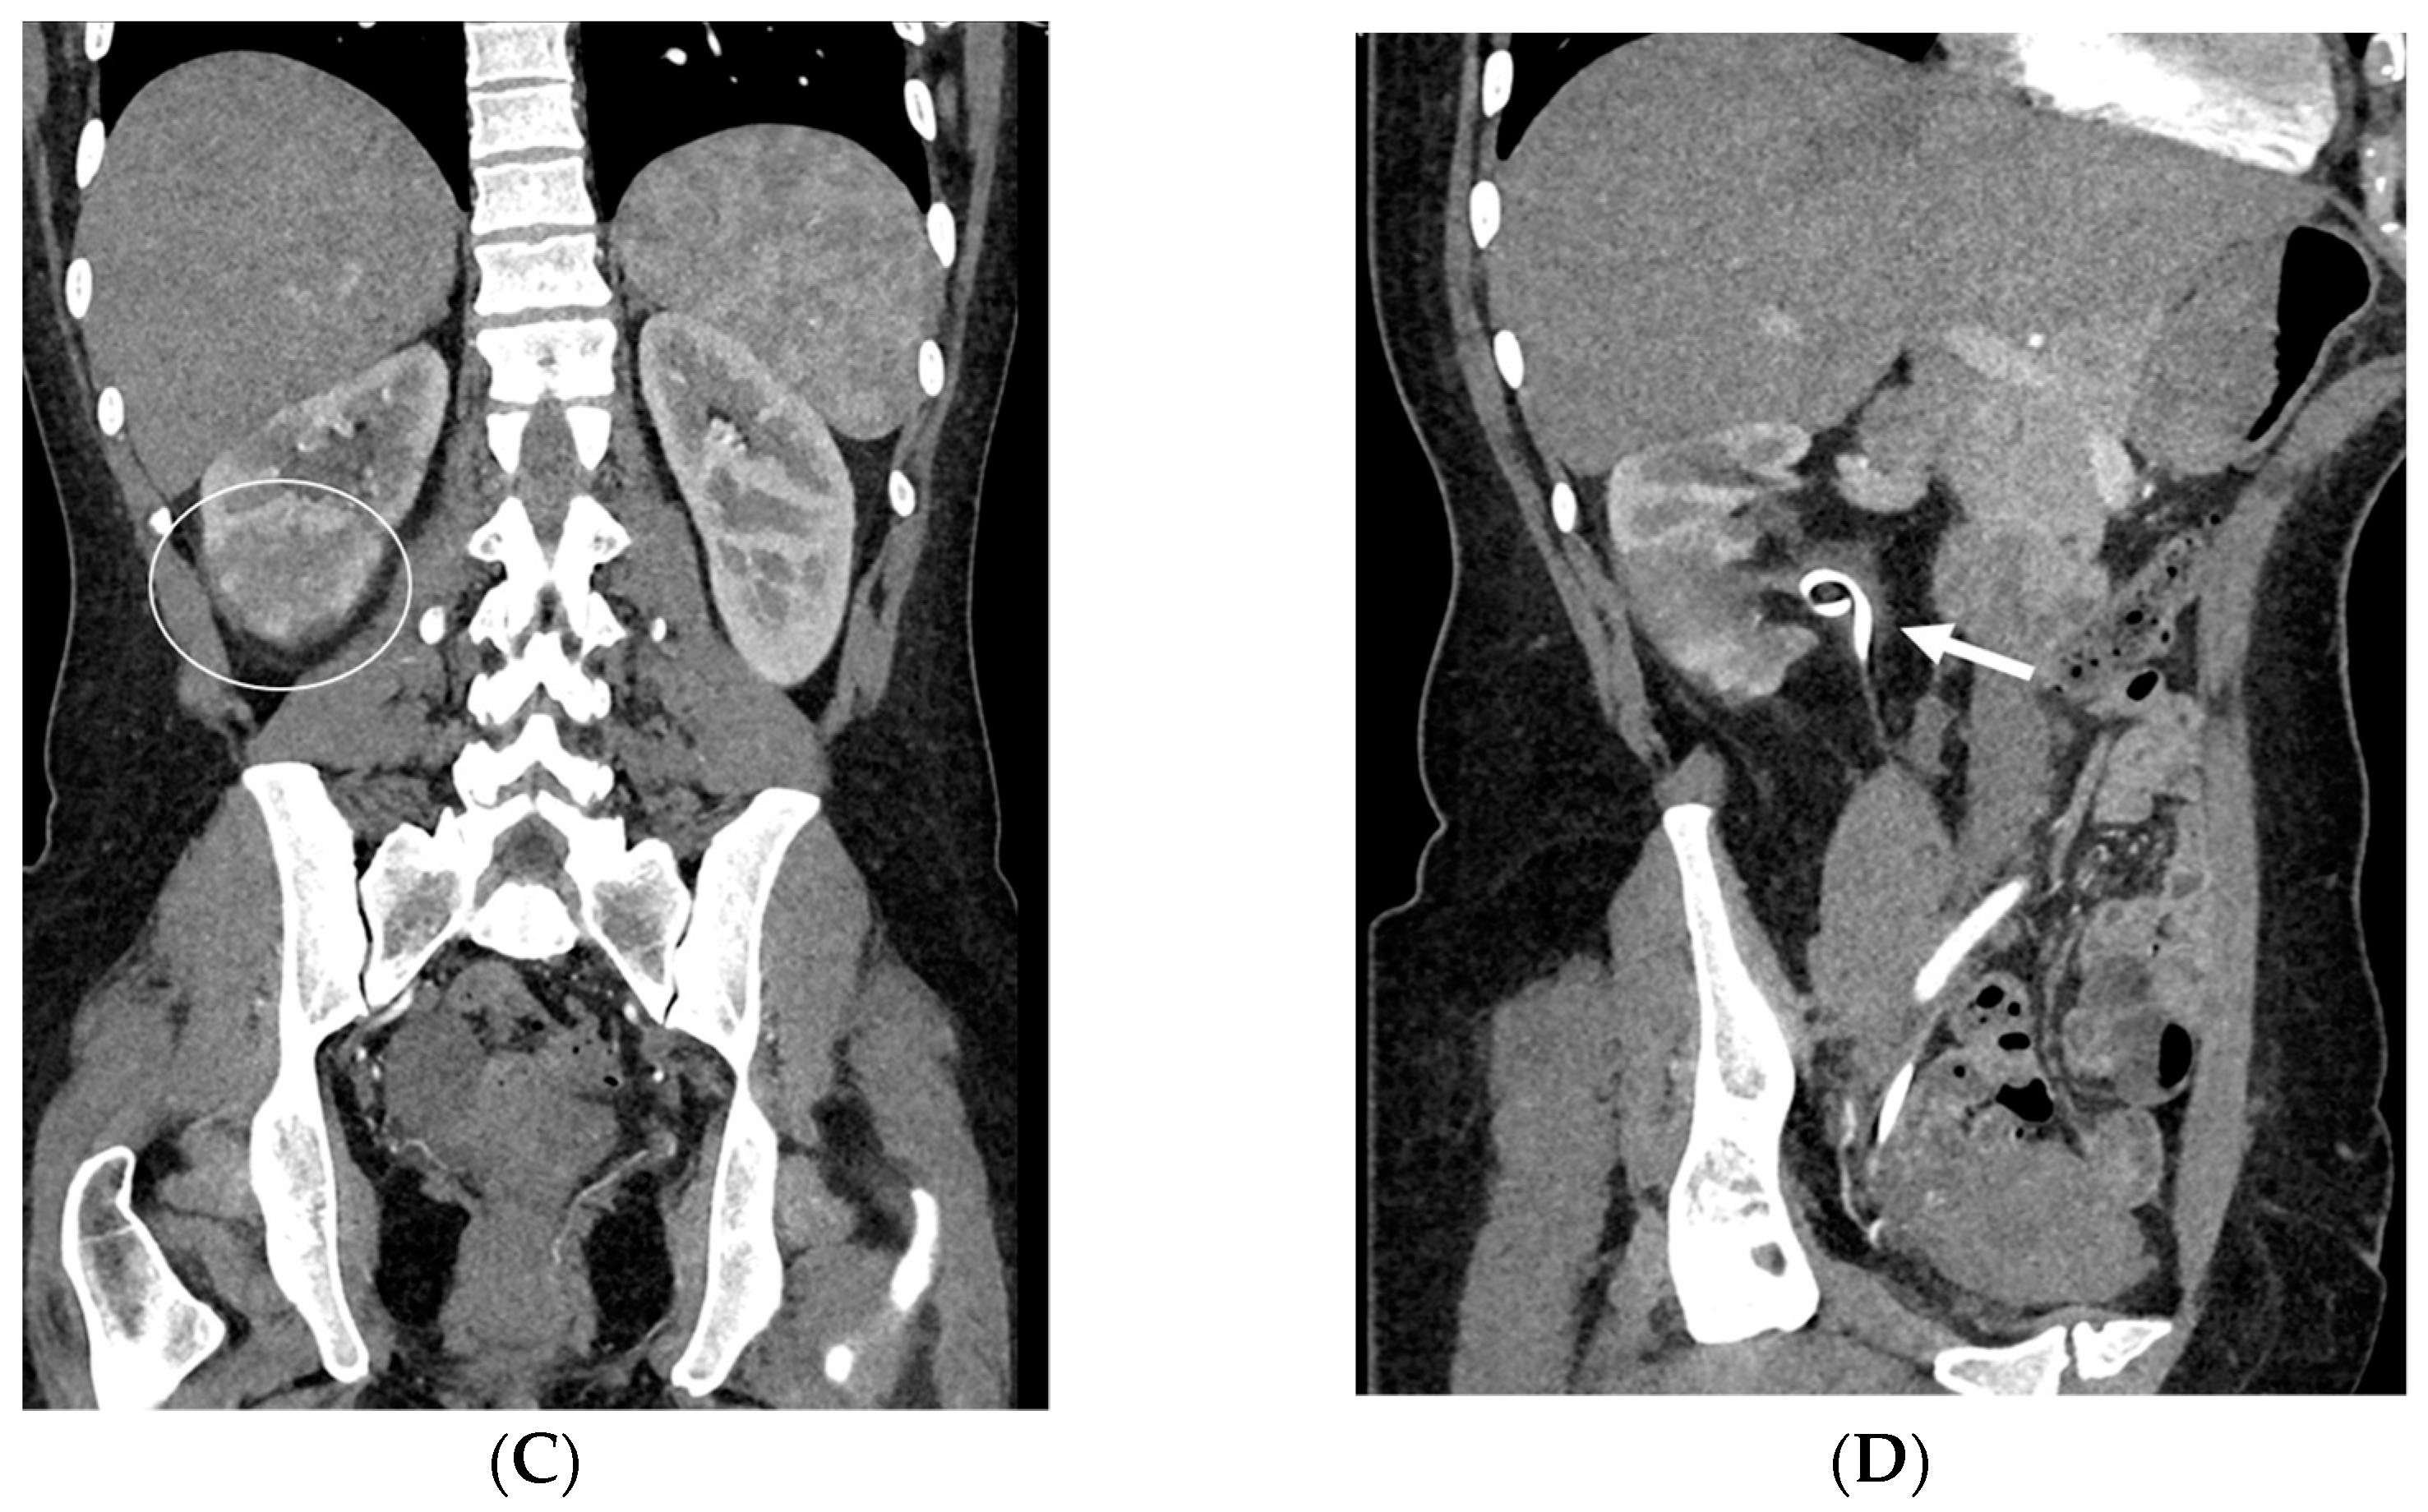

- Malposition: The malposition of a stent is defined as an incorrect position relative to initial placement, while displacement presents a subsequent occurrence in a device that was previously located in the correct position. A stent improperly positioned might assume a sub-pyelic position when the proximal end fails to reach the renal pelvis and a supravesical position when the distal end is detected within the ureter. The origins of this complication predominantly stem from the placement technique, whether it be endoscopy- or fluoroscopy-guided insertion. This underscores the need to verify the accurate positioning of the stent post-placement. Ensuring an adequate length is essential to reduce the occurrence of this complication (Figure 2, Figure 3, Figure 4, Figure 5 and Figure 6) [21,22].

- Stent Knotting: It is a rare complication. Most of these knots involve the proximal end of the stent near the coil, but every portion can be affected [27,28]. Previous reports have attributed knot formation to the excessive length of the stent, stent shape (double-J or multicoil), and flexibility or anatomical abnormalities, such as cystocele and ileal conduits. An abdominal X-ray and, especially, a CT scan are more sensitive than other imaging modalities in identifying a ruptured or knotted stent as well as its migration (Figure 7) [29,30].